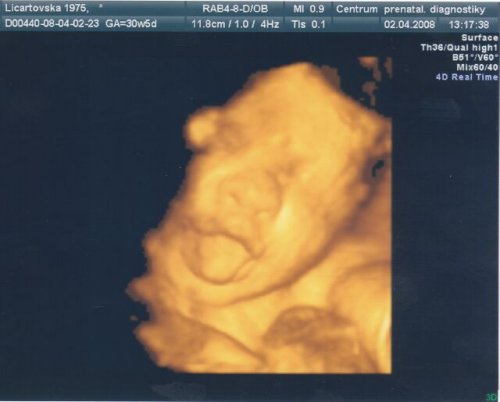

Licina

•  27 fotek